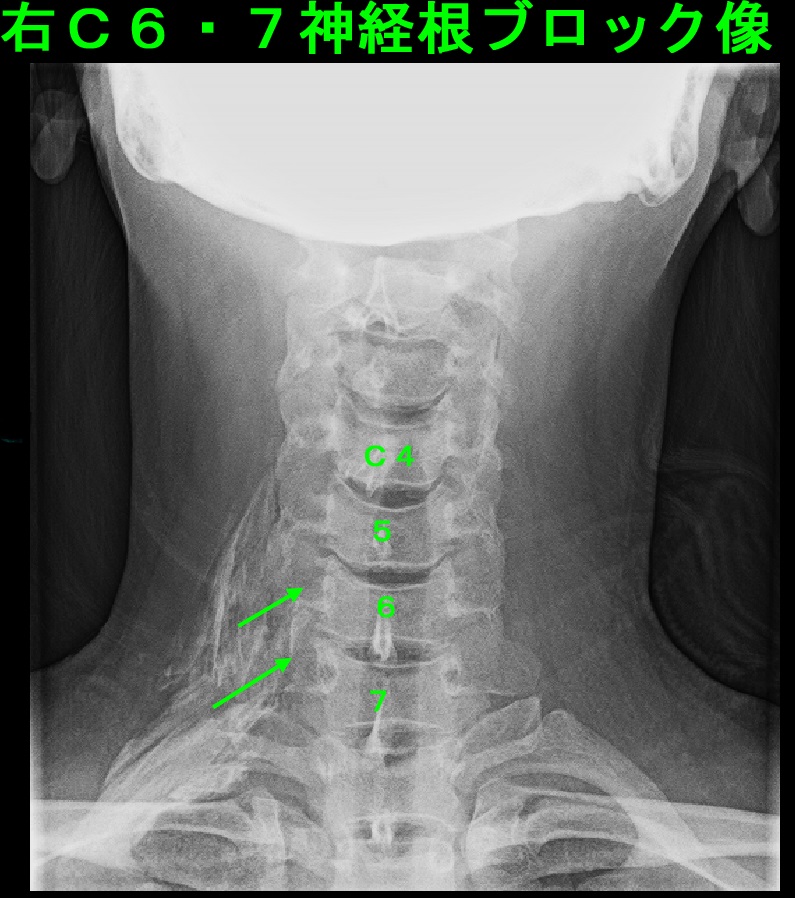

症状が重度のため、最も効果が期待できる頚椎神経根ブロックの治療を勧めたところ、

患者さんが同意されたので、初診時に施行しています。

患者さんのブロックの感想は、いつもかかりつけ整形外科の局所注射より全然痛くなかったとのことでした。

6日後の再診時には、痛み(ブロック前を10として)10→0→2と経過していました。